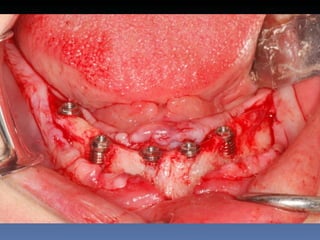

Maria Seemagenn Borges

Diagnóstico: Desdentada

Plano de tratamento: Instalação de 5 implants endo-

ósseos - “Protocolo Branemark”, com carga imediata.